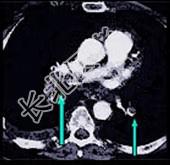

- 多项选择题患者男,突发胸部疼痛, 进行性呼吸困难1小时,行X线片检查, 提示右下肺病变,急诊CT平扫加增强, 如图所示 ( )

B、SCT增强扫描示右侧肺动脉主干完全性充盈缺损

C、右肺动脉开口处见不规则软组织密度影

D、考虑为右侧肺动脉(中央性)栓塞